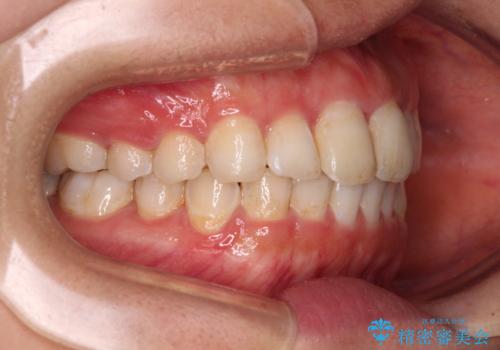

前歯の捻れを改善 インビザラインによる矯正治療

- 前歯の翼状捻転を気にして来院された患者様です。

全体的に叢生は軽度であったため、インビザラインにて矯正治療を行うこととしました。

前歯の幅の大きさも気になっていたため、IPRにより叢生を解消するとともに、歯の大きさも改善しました。